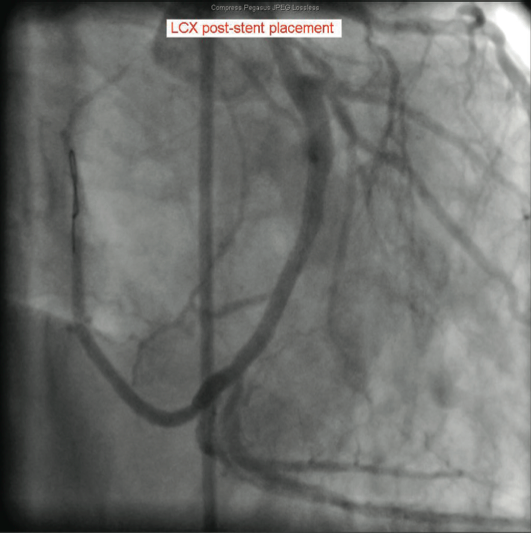

The catheterization and angiogram showed a patent left main coronary artery that bifurcated into the left anterior descending (LAD) and the left circumflex (LCX). The LAD had a mid 50% stenosis and the LCX was a large-sized vessel that gave off three obtuse marginal (OM) branches and continued distally into the right

side of the heart, filling the right coronary artery (RCA) from the distal end retrograde. The LCX had a mid 70-80% lesion that was confirmed by intravascular ultrasound (IVUS). The right coronary artery had no ostium and received retrograde filling via the LCX, continuing distally into the right myocardium. The LCX 80% mid stenosis was successfully revascularized with deployment of two drug-eluting stents. The patient was placed on post-procedure clopidogrel, simvastatin, beta blockers, and nitroglycerin.